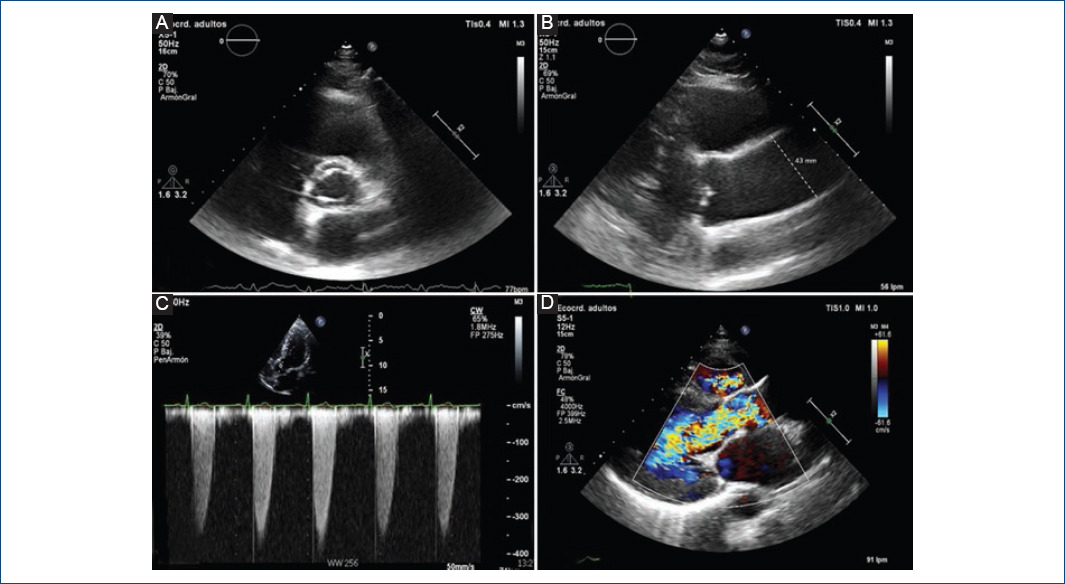

La complicación más frecuente en los pacientes con VAB es la disfunción valvular por estenosis o insuficiencia1,3 (Fig. 3). En la infancia, el curso típico es asintomático. En la juventud y la primera edad adulta, la mayor parte de las consultas y de las intervenciones quirúrgicas son por insuficiencia aórtica grave23,24. El mecanismo etiológico puede ser funcional, por dilatación de la raíz de la aorta, o primario valvular por prolapso, degeneración mixomatosa o endocarditis. Posteriormente, los individuos suelen desarrollar estenosis aórtica por un proceso de calcificación valvular acelerada, precisando intervención a una edad 20-30 años menor que los pacientes con VAT estenóticas23-26. Desde el punto de vista morfológico, la calcificación parece suceder de manera similar a lo que ocurre en la VAT. Las investigaciones actuales tratan de dilucidar si la variabilidad en la edad de presentación de la calcificación en la VAB respecto a la VAT se debe predominantemente a factores mecánicos o genéticos1,15. El manejo de la estenosis aórtica y de la insuficiencia aórtica debe ser el mismo en los pacientes con VAB que en aquellos con VAT, siguiendo las guías de práctica clínica actuales14,27,28.

Figura 3 Imágenes de ecocardiograma transtorácico. A: visión en paraesternal en el eje corto en la que se observa una válvula aórtica bicúspide de tipo 1 (fusión de los velos coronarianos derecho e izquierdo) abierta en sístole. B: plano a nivel de la raíz de la aorta y la aorta ascendente que evidencia una importante dilatación aórtica (43 mm). C: gradiente transvalvular aórtico mediante Doppler continuo que muestra velocidades y gradientes elevados propios de una estenosis aórtica significativa. D: mediante Doppler color se ve un chorro de regurgitación diastólico que ocupa todo el tracto de salida del ventrículo izquierdo, propio de una insuficiencia aórtica grave, en un paciente con valvulopatía bicúspide.